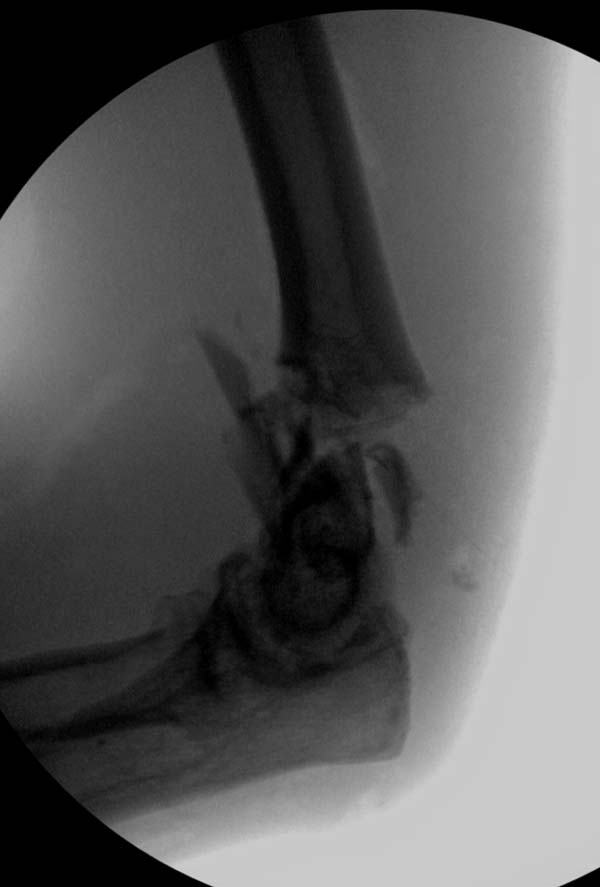

Примеры: первому более 15 лет фиксирован шурупом и tension band

technique, а второй перелом открытый больной 80 лет, после наружного

фиксатора в первом этапе и окончательная фиксация вторично. Третьий раз

внесуставная остеотомия...

Вложение не в текстовом формате было извлечено&hellip;

Имя     : 1-3 old humerus distal.JPG

Тип     : image/jpeg

Размер  : 31506 байтов

Описание: отсутствует

Url     : http://weborto.net:8080/pipermail/ortho/attachments/20130604/c45a379f/attachment-0006.jpeg